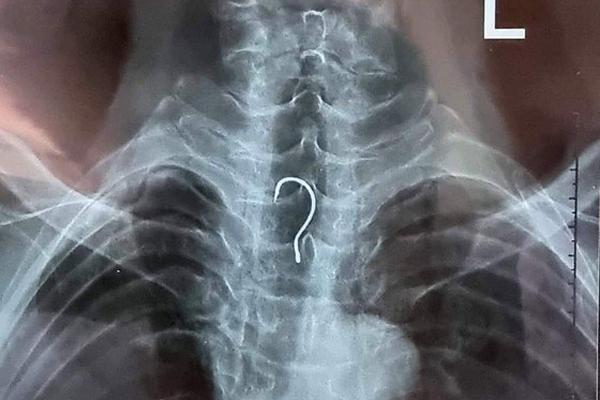

Chiếc lưỡi câu dài khoảng 4 cm nằm trong thực quản của cụ ông 83 tuổi.

Tại đây, bệnh nhân T.V.A. được các bác sĩ cho chụp phim X-quang và chỉ định nội soi thực quản - dạ dày - tá tràng không sinh thiết.

Qua kết quả nội soi, các bác sĩ phát hiện dị vật nằm ở trong khu vực thực quản của bệnh nhân.

Ngay sau đó, ê-kíp nội soi đã gắp ra ngoài dị vật là một chiếc lưỡi câu có chiều dài khoảng 4cm, vòng cung rộng gần 1,5cm.